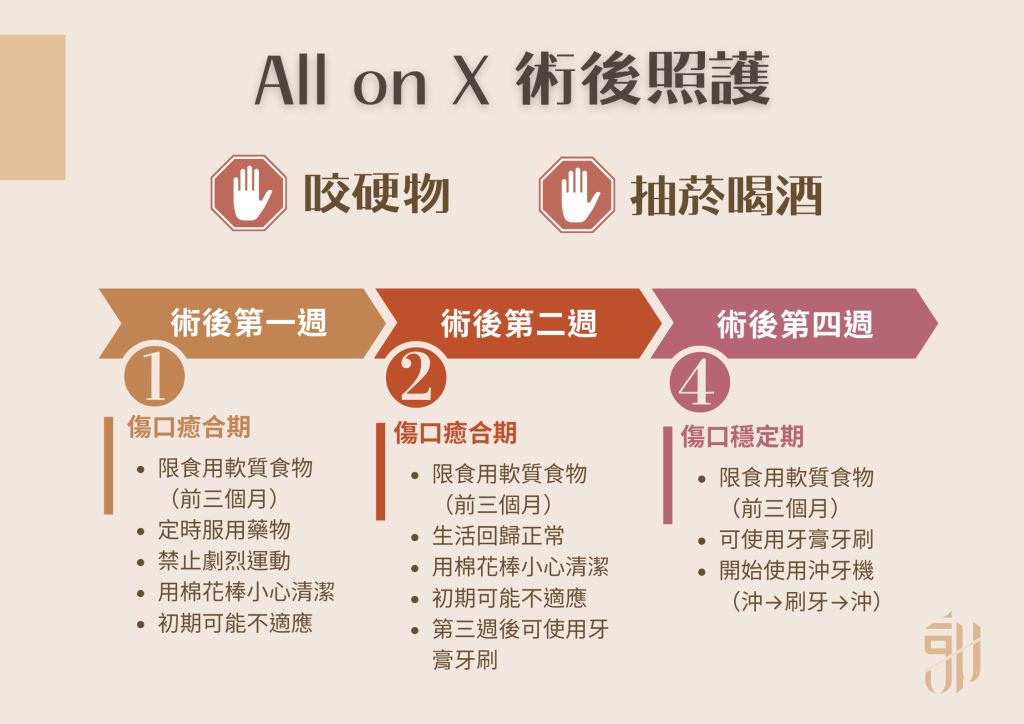

術後傷口照護至關重要,傷口照護不佳可能會影響傷口癒合和植體骨整合狀況,郭光哲醫師統整出以下不同時間點需要注意的事項給病患參考。

- 咬合力量限制:接受 All on X 患者若有接出臨時假牙,在前三個月必須非常注意咬合力道,因為前三個月剛植入的植體周圍骨頭還在癒合生長,過大的咬合力量可能會導致植體周圍骨頭萎縮甚至植體失敗。前三個月食物部分限制以軟質食物為主,若是軟的塑膠湯匙無法分開的食物都被歸類在硬的或韌的食物,都應該避免。如果夜間磨牙患者,需搭配咀嚼肌肉毒桿菌注射。禁止咀嚼口香糖。剛裝上的臨時假牙,因口腔還不適應,咬合不習慣、講話不清楚都是常見的初期問題,等口腔習慣後咬合和說話都會回歸正常。

- 禁止抽菸、飲酒:抽菸已有直接證據會導致植體早期失敗。All on X 技術中每根植體的支撐都非常重要,只要其中一根植體出現問題都有可能造成全部植體連帶影響而失敗,抽菸患者也會喪失所有植體保固,傷身又傷財。飲酒會造成牙齦組織癒合受到影響,可能造成骨頭外露、植體外露的狀況,大幅度降低植體使用年限,手術後兩週內嚴格禁止飲酒。

- 手術完成後第一週:飲食除了食用軟質食物之外,定時服用郭光哲醫師開立之藥物(千萬不能因為感覺還好選擇自行停藥),避免太燙、太辣、太刺激的食物,避免劇烈運動、重量訓練(會喘的運動都須避免)。清潔部分可使用棉花棒沾漱口水輕柔地擦拭臨時假牙和牙齦,飯後含漱口水(第一週切忌用力漱口)。

- 手術完成第二週:飲食持續食用軟質食物,郭光哲醫師會在回診檢查時確定傷口狀況及咬合情形。在傷口正常癒合的狀況下,生活運動可以回歸正常。清潔部分持續使用棉花棒沾漱口水輕柔地擦拭臨時假牙和牙齦直到第二週結束。第三週開始回復使用牙刷和牙膏清潔。

- 手術完成第四週:飲食持續食用軟質食物,郭光哲醫師會在回診檢查時完全拆除縫線及咬合情形,並根據每個病人的狀況給予新的清潔指示。一般正常情況三餐飯後睡前可以正常使用牙刷牙膏清潔,All on X 的臨時假牙下可能會因為牙齦消腫後開始出現縫隙,建議開始使用沖牙機清潔(清潔口訣:沖→刷→沖,先用沖牙機將大塊食物殘渣沖出,在正常刷牙,刷完牙之後再沖牙一次確保牙菌斑完全清潔乾淨)。